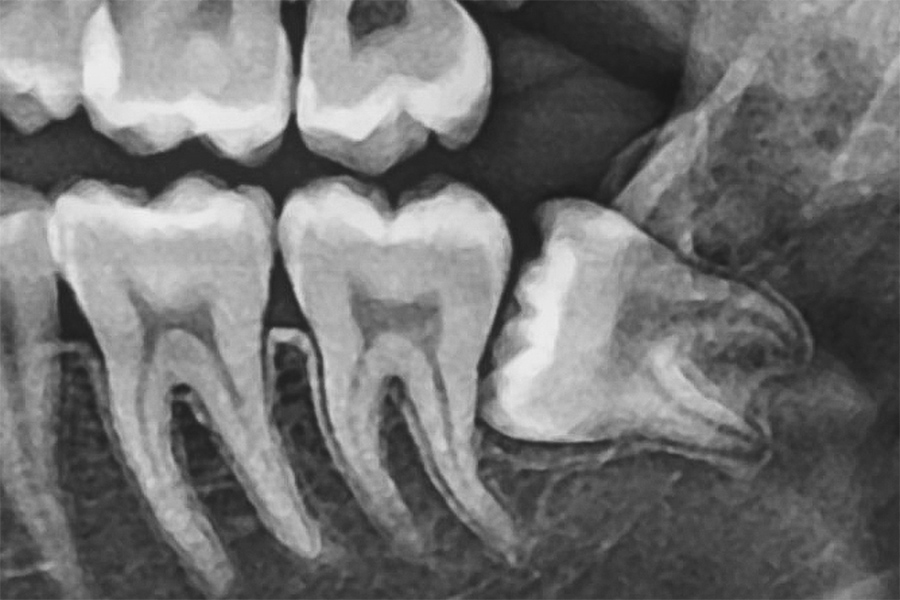

「パノラマレントゲン」による全体把握

パノラマレントゲンは、お口全体を1枚の画像として確認できる撮影方法で、親知らずの位置や向き、周囲の歯との関係を総合的に把握できます。特に下あごの親知らずは、下歯槽神経と呼ばれる重要な神経の近くにあることが多いため、抜歯前のリスク評価が非常に重要です。パノラマ撮影により、神経との距離や重なり具合を事前に確認し、より安全性の高い治療計画につなげています。